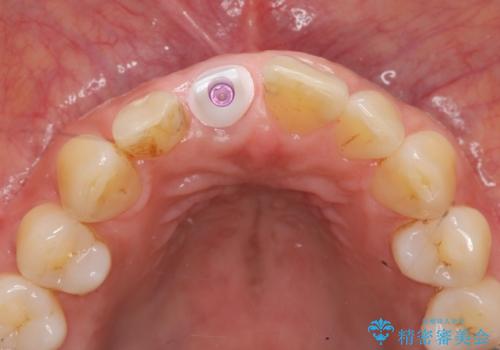

骨造成を伴う前歯のインプラント治療

審美的・機能的に良好な位置に埋入するには、骨量が十分ではなかったため骨の造成を併用したインプラント埋入外科手術を行います。

前歯のインプラントを審美的に仕上げるには、インプラント周囲に十分な骨の量と厚みのある歯肉、そして埋入位置の精密な位置付けが重要です。